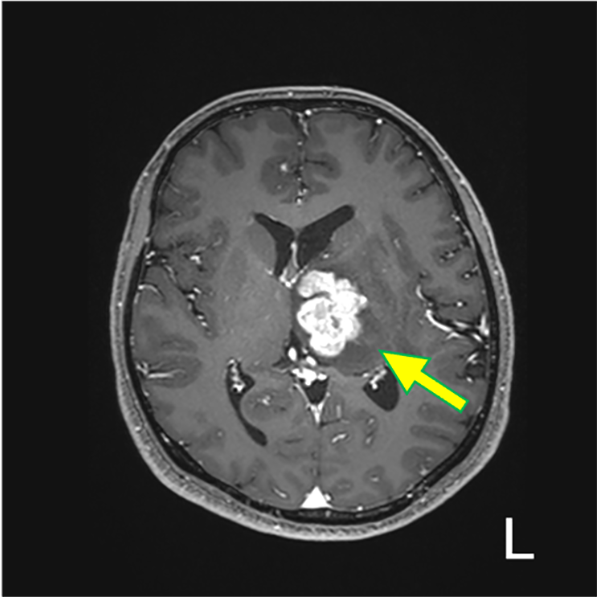

図1.T1WI(Tra.)

左視床を中心に、やや不均一な灰白質と同程度の信号を呈する腫瘤を認める(矢印)。mass effect を呈し、軽度の大脳鎌下ヘルニアを生じている。

図5.造影後 T1WI (Tra.)

T2強調像で認めた分葉状の実質部が強く造影されている。内部に小さな造影欠損を伴う(矢印)。松果体原発では無いと考えられる。